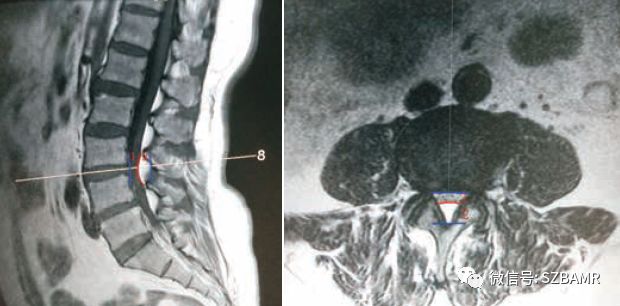

• 椎管内硬膜外脂肪增多症与终丝脂肪沉积

椎管内硬膜外脂肪增多症与终丝脂肪沉积

• 常见易忽略的疾病—椎管内硬膜外脂肪增多症

常见易忽略的疾病—椎管内硬膜外脂肪增多症

• 椎管内硬膜外脂肪增多症

椎管内硬膜外脂肪增多症